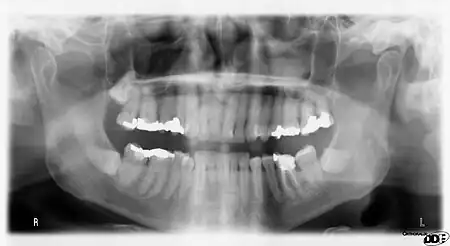

A panoramic radiograph is a panoramic scanning dental X-ray of the upper and lower jaw. It shows a two-dimensional view of a half-circle from ear to ear. Panoramic radiography is a form of focal plane tomography; thus, images of multiple planes are taken to make up the composite panoramic image, where the maxilla and mandible are in the focal trough and the structures that are superficial and deep to the trough are blurred.